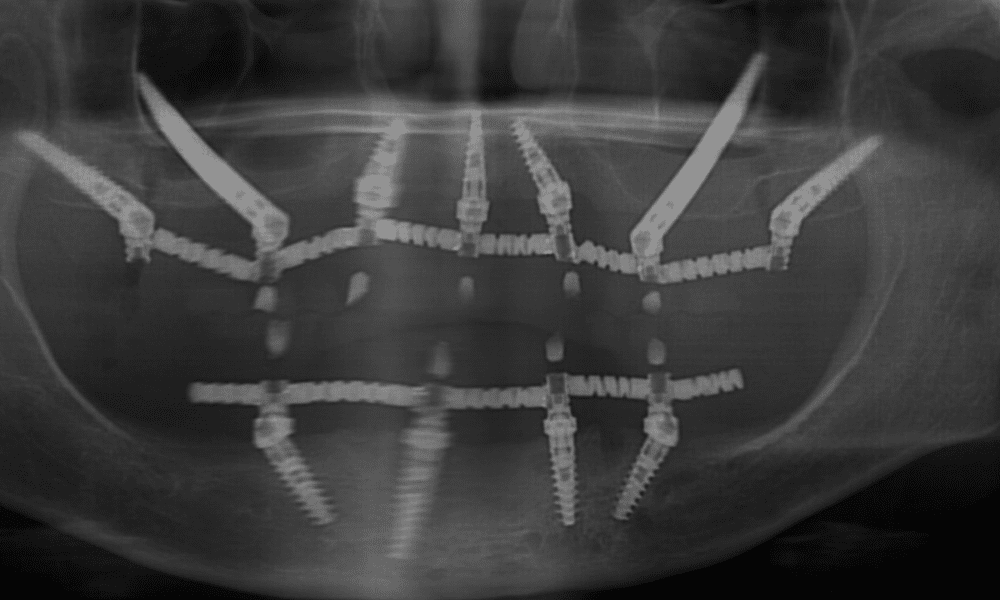

שתלים זיגומטיים הם למעשה שתלים דנטליים ייחודיים שנועדו להתמודד עם בעיית חוסר עצם בלסת העליונה, מבלי שיהיה צורך בהשתלת עצם או הליך מורכב כמו הרמת סינוס.

בשתלים רגילים, השתל מוברג לתוך עצם הלסת, שצלים זיגונטיים, לעומת זאת, הם שתלים ארוכים יותר משתלים רגילים ומגיעים אל מעל לאזור הלסת. כלומר אל עצם הזיגומה – העצם שממוקמת בחלק העליון של הלחי, היכן שנמצאת הגבעה של הלחי.

עצם הזיגומה היא עצם חזקה שנמצאת במיקום מדוייק מעל הפה שלנו ולכן מתאימה לעיגון של שתלים דנטליים.

השתלה זיגומטית מצריכה מיומנות גבוהה מצד הרופא, שכן על הרופא להחדיר את השתל בצורה מדויקת אל תוך עצם הזיגומה.

בתהליך זה, הרופא נדרש לבצע חיתוך מדויק של החניכיים, ולאחר מכן להחדיר את השתל הזיגומטי לעמקי העצם הזיגומטית. בעזרת שתלים ארוכים יותר וברגים מיוחדים, השתל "ננעץ" בתוך העצם בצורה יציבה ומאפשר עיגון מוצלח של השיניים.